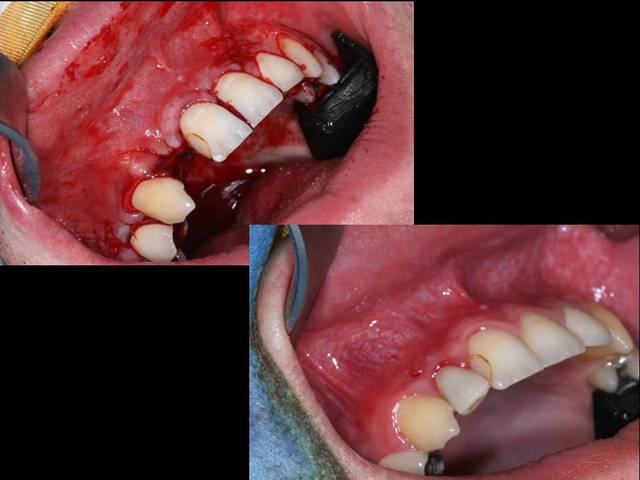

Salut je poste un cas d'un kyste à priori d'origine dentaire avec ROG pour éviter d'avoir un effondrement de la paroi vestibulaire avant pose implantaire.

Comblement au béta TCP pour permettre une résorption totale et un remodelage de la voussure vestibulaire

sur la dia 6, dernière photo, c'est l'implant avec une MCI ?

tu as utilisé la dent évidée ??

Pourquoi préfères tu le Beta TCP à l'allogénique ici, ou à une Xénogreffe comme le Bio-Oss ?

Je souhaite avoir une résorption de la voussure vestibulaire donc exit le Bio-oss et après vu que la cavité est quasi fermée, je me dis qu'il n'est franchement utile d'utiliser de l'allogénique.